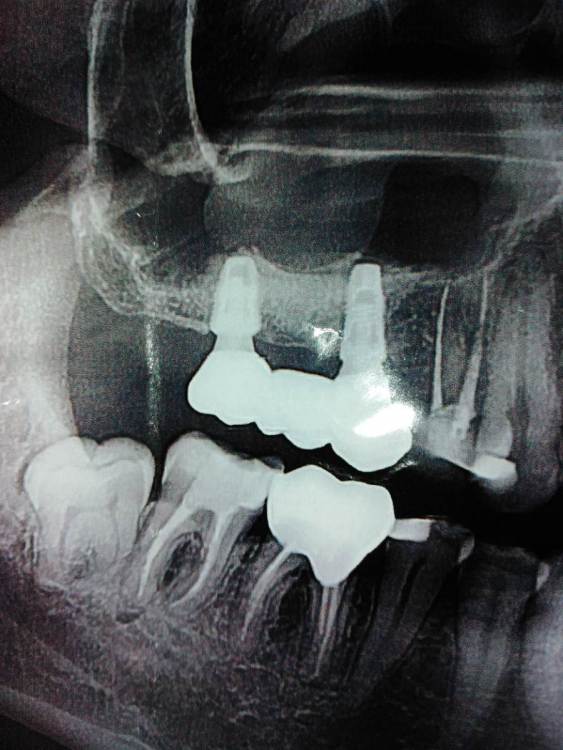

еатегsffhgj Опубликовано 29 июля, 2021 Автор Поделиться Опубликовано 29 июля, 2021 Ссылка на комментарий

еатегsffhgj Опубликовано 6 сентября, 2021 Автор Поделиться Опубликовано 6 сентября, 2021 (изменено) сходил к врачу. он вытащил несколько крошек. говорит,или крошка,которая снаружи добавлялась не прижилась,или из пазухи выдавливает. кт он не видел. только панораму. крошки вытащил,но дальше не смог расковырять. кость твердая,вроде. надо ему принести кт? как вы думаете,какой вариант наиболее вероятен?. сказал показаться в конце недели. Изменено 6 сентября, 2021 пользователем еатегsffhgj Ссылка на комментарий

Irouil Опубликовано 7 сентября, 2021 Поделиться Опубликовано 7 сентября, 2021 Вероятность несостоятельности имплантата в Вашей ситуации исчезающе мала прорезавшаяся крошка - это часть «порошка», которым заполняли костные дефекты. Процесс этот, обычно, очень компактный, в дефекты его достаточно надежно «трамбуют». Но одна-другая крупинка могут сбежать в толщу раны и тогда, рано или поздно, они вылезут на поверхность, чем их приключения и закончатся - как произошло в Вашем случае. А из какого именно дефекта данный беглец улизнул я значимой разницы не вижу 1 1 Ссылка на комментарий

еатегsffhgj Опубликовано 28 сентября, 2021 Автор Поделиться Опубликовано 28 сентября, 2021 ходил к хирургу сегодня по поводу удаления 8. прощупал,удалять буду само собой,но к моей боли он отношения не имеет. опять же по словам хирурга. сделал разрез десны что то просверлил в кости. у 7 зуба. в момент сверления была как раз та боль,которая у меня всегда,только сильнее раза в два. назначил антибиотики. поставил резинку. говорит,что должно быть легче. пока я не понял,легче,или нет. короче,жесть какая то. сегодня снимок сделал Ссылка на комментарий

Irouil Опубликовано 30 сентября, 2021 Поделиться Опубликовано 30 сентября, 2021 @еатегsffhgj свежий снимок никак не отличается от старого и, в принципе, отличаться не должен. Изменения на снимке наблюдают через 6 месяцев после окончательной пломбировки, а у Вас, насколько я понял из всего описанного, она пока не выполнена. Идти надо было (и надо сейчас) к терапевту, который зуб лечит, а не к хирургу. Решение о прогнозе сохранения этого зуба принимать именно ему. Вы спрашиваете советы, потом поступаете наоборот и каждый раз задаетесь вопросом почему ничего не помогает. Я не знаю (и навряд кто-нибудь здесь знает) зачем Вам «что-то там посверлили в кости», разрезы выполняются для снятия обострения. Идите к стоматологу-терапевту, все остальные действия предпринимайте основываясь на его рекомендациях 1 Ссылка на комментарий

еатегsffhgj Опубликовано 1 октября, 2021 Автор Поделиться Опубликовано 1 октября, 2021 (изменено) кстати,когда мне вымыли кальций, показали снимок прицельный, оказалось,что в одном корне в верхушке инструмент, еще один корень с двумя каналами,один из которых не был обнаружен с помощью микроскопа. скорее всего будут удалять. а,вы говорите иди к терапевту. по поводу просверленной кости,я уточнил. мне сделали разрез на десне, и в кортикальной кости,т.к она очень плотная. сейчас этот канал прошли. предлагают кальций опять попробовать,но смогу ли я еще терпеть эту боль - не знаю. Изменено 1 октября, 2021 пользователем еатегsffhgj Ссылка на комментарий